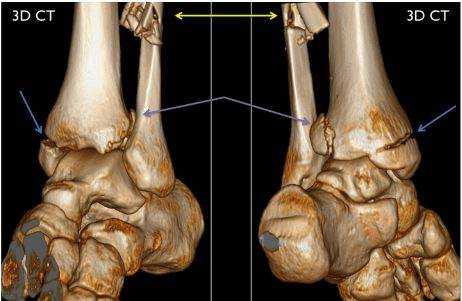

3D-модель голеностопа (вид спереди и сзади). Стрелками указаны места переломов